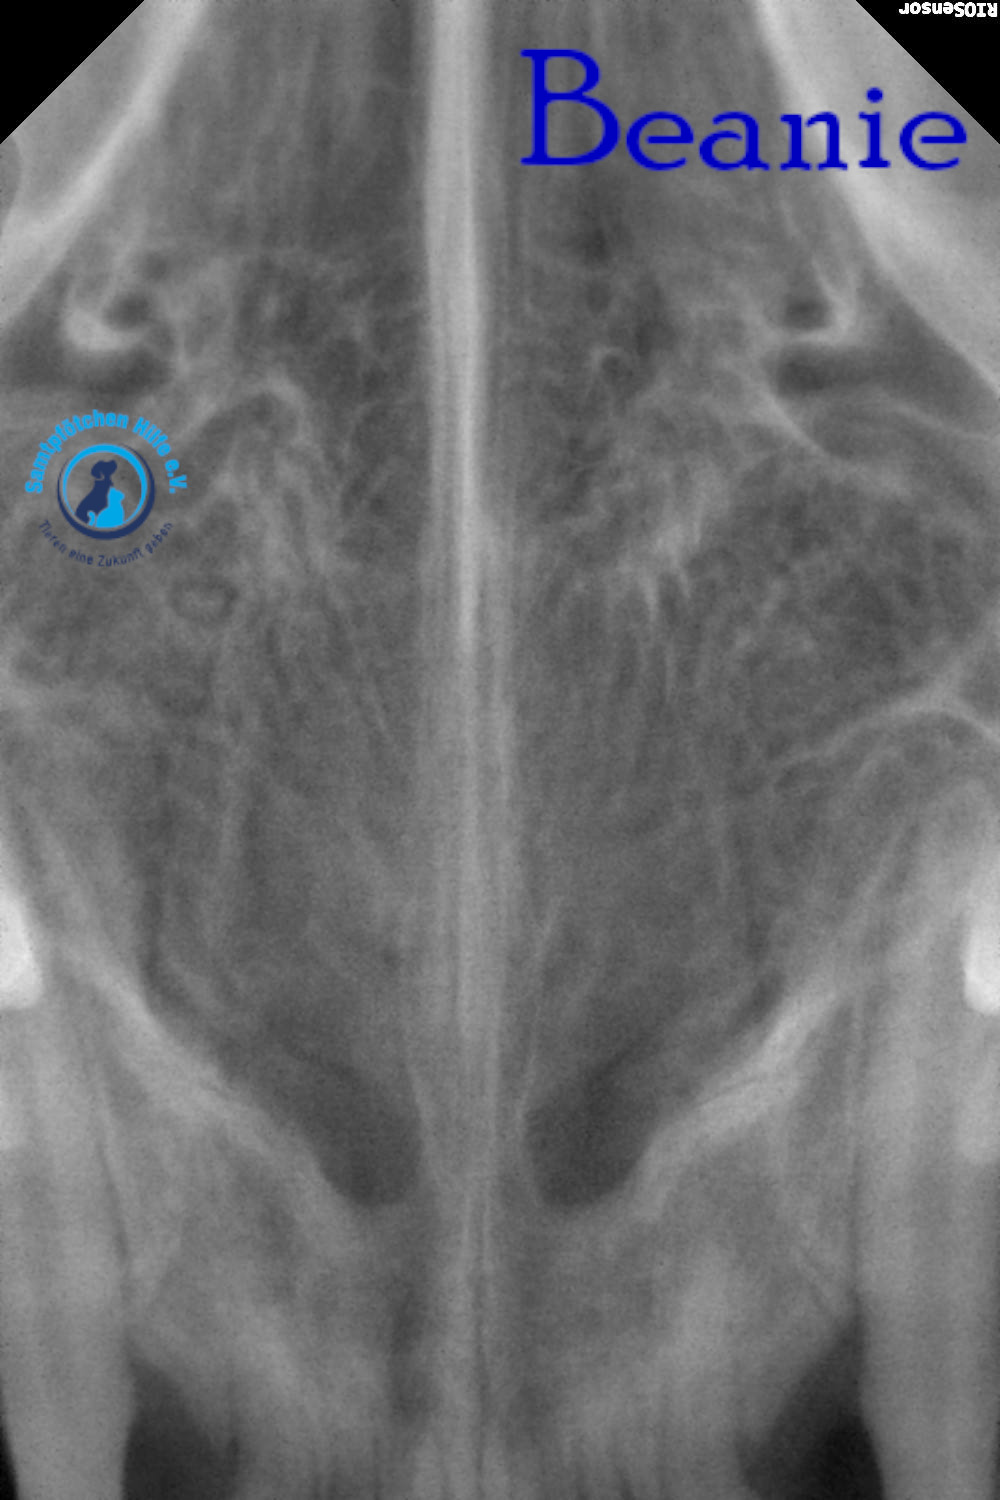

Unsere Beanie hat immer noch Probleme mit der Nasenatmung und musste deshalb zum Tierarzt. Der Arzt nahm Blut für allgemeine Indikatoren und Biochemie sowie PCR für Leukämie und Immunschwäche ab. Auch die Ohren wurden sorgfältig untersucht; Manchmal behindern Polypen in den Ohren die Atmung, aber die Ohren waren sauber. Der Arzt untersuchte auch den Rachenraum. Aufgrund der Untersuchungsergebnisse wurde eine Computertomographie des Gehirns im Bereich der Nase und des Nasenrachens sowie eine tägliche Zahnreinigung verordnet – bei Beanie besteht der Verdacht auf eine juvenile Stomatitis. Wenn Sie jetzt nicht mit der Zahnbehandlung beginnen, müssen in 2-3 Jahren alle Zähne gezogen werden.

Lyudmila schreibt: "Die Ärzte vermuteten, dass etwas in Beanies Nasenrachenraum feststeckte, ein Fremdkörper, der sie am Atmen hinderte. Sie führten eine Operation durch, führten eine Sonde tief ein und spülten sie aus, konnten aber nichts finden. Eine Röntgenaufnahme zeigte leichte Veränderungen in einer Nasennebenhöhle. Außerdem wurde Material aus der Nasenschleimhaut für eine Zytologie entnommen. Das Fazit des Zytologen: Das Material könnte auf einen Polypen in der Nase hinweisen. Da Binis Nasengänge sehr eng sind, ist eine Rhinoskopie möglicherweise nicht möglich. Bisher wurden Hormontropfen in die Nase empfohlen, die aber kaum helfen. Eine Konsultation mit einem Chirurgen, der Rhinoskopie durchführt, ist erforderlich; unsere Tierklinik führt diese Untersuchung nicht durch.